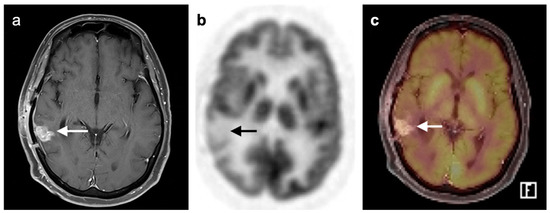

3.4. CNS Lymphoma

3.6. Response to Therapy